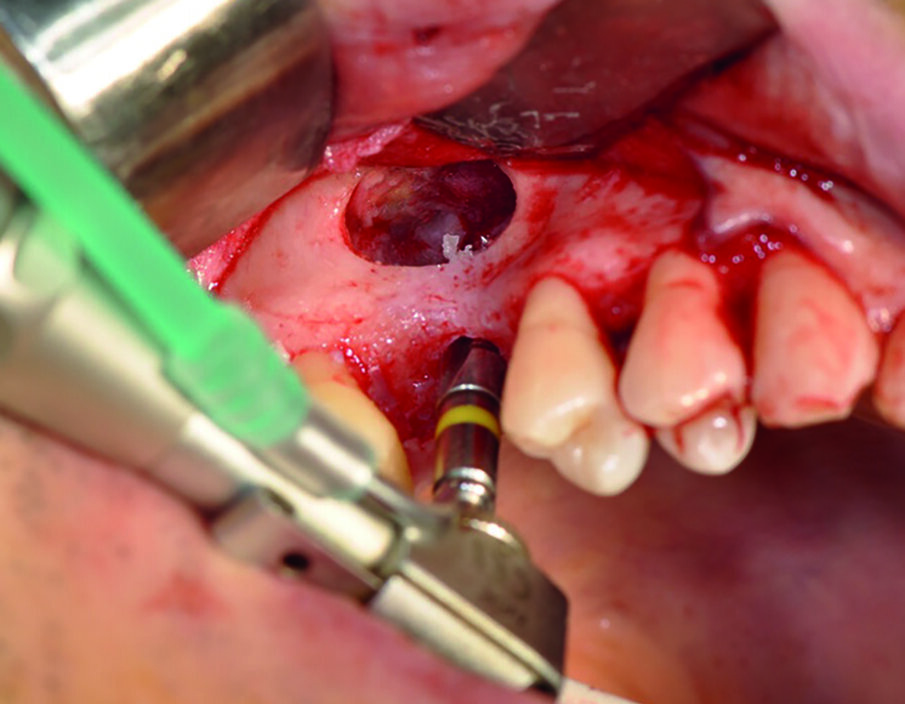

A due mesi dall’estrazione all’esame radiografico si evidenzia una mancanza di osso tale da ritenere necessario, per poter inserire un nuovo impianto, un intervento di grande rialzo del seno mascellare. La lastra mostra, inoltre, la presenza di tre mm di osso residuo che mi permettono di inserire contestualmente al grande rialzo del seno un impianto way milano 4,5 per 10 mm, stabilizzato in osso nativo. Previa anestesia, si procede con incisione in cresta procedendo intrasulculare da 14 a 17 (Fig. 2).

Avendo deciso di inserire l’impianto, l’incisione in cresta si rende necessaria perché più idonea rispetto ad una incisione laterale in mucosa libera. Successivamente si pratica con una fresa a pallina diamantata, montata su manipolo dritto con irrigazione, l’osteotomia laterale sulla parete del seno mascellare per poter accedere alla membrana di Schneider.